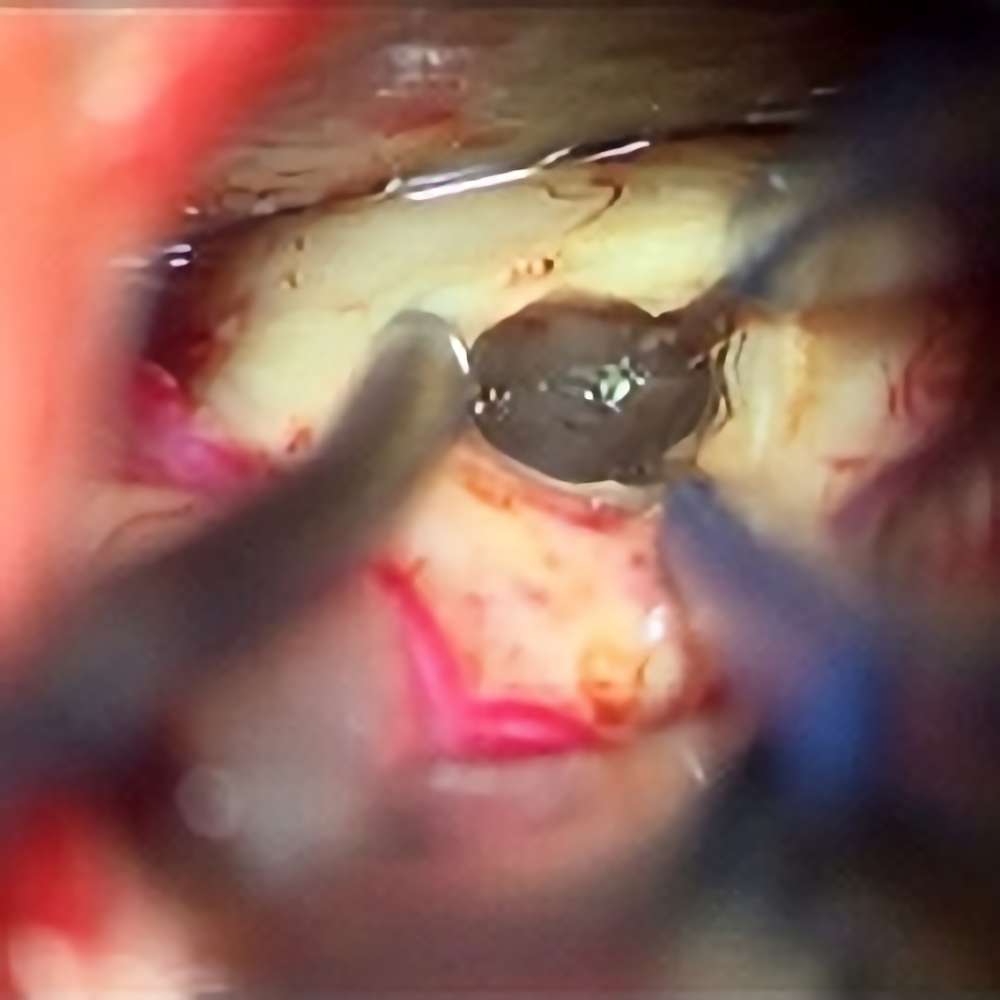

285

'22年4月

70代

膠芽腫

頭蓋内腫瘍摘出術

No.’22_42 摘出 前

No.’22_42  摘出 中

No.’22_42 摘出 後